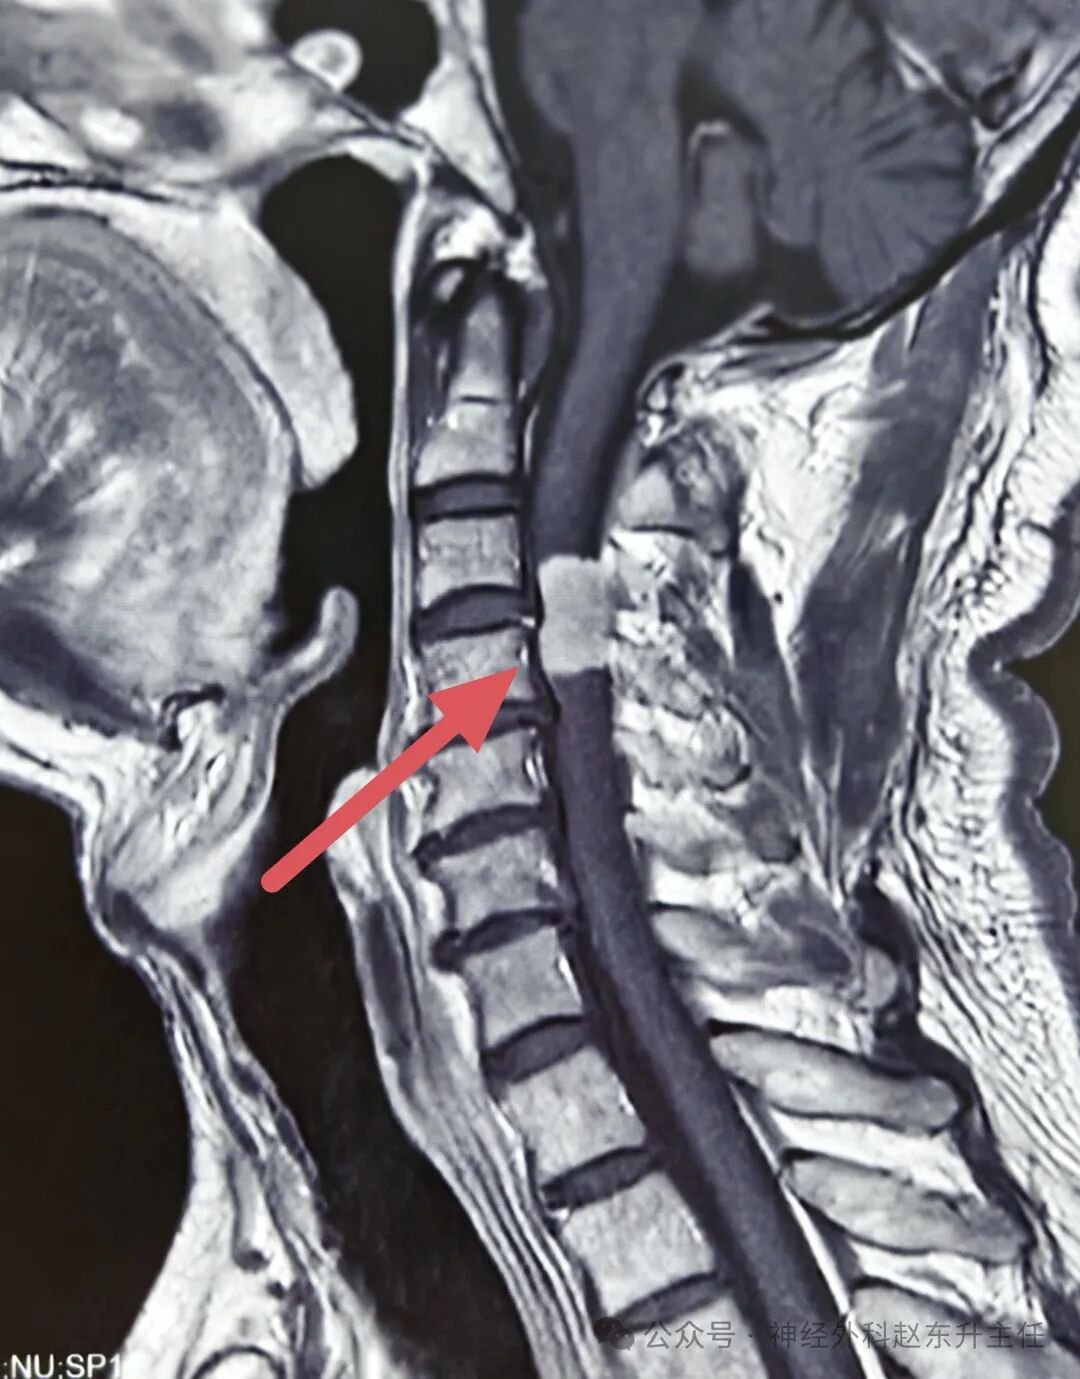

姚先生4月前感觉双手麻木,右手较明显,且持续加重,无颈肩部及上肢疼痛,在当地医院查颈椎MRI提示颈3-4椎管内肿瘤,肿瘤将近2cm大小,严重压迫脊髓。患者本身合并高血压,最高达170/105mmHg,看到这个结果,患者非常担心,随后找到西安市红会医院神经外科赵东升主任,赵主任看过片子后认为患者椎管内肿瘤为良性,手术可一次性治愈,建议手术治疗,家属在反复思想斗争下决定让赵主任主导手术。

IMG_20250530_155434.jpgIMG_20250530_155452.jpgIMG_20250530_155409.jpg术前磁共振增强显示肿瘤较大,质地较硬,压迫脊髓明显

手术在全麻下进行,使用高倍显微镜仔细剥离肿瘤,术中电生理监测,未损伤神经,并且将肿瘤完全切除。术后病理提示为神经鞘瘤。